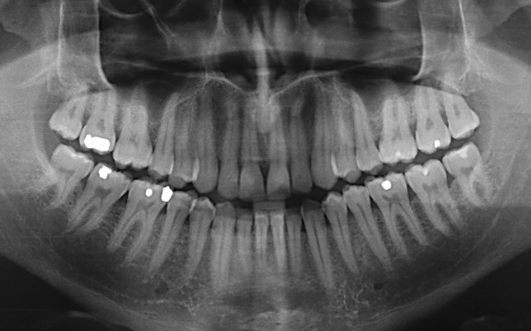

Full panoramic X-rays

A panoramic X-ray gives you the image of your entire oral structure in one single image. This type of X-ray is like an overview of your oral health. Upper and lower teeth, jaws, joints, and their supporting bone along with nerves and sinuses are all depicted in panoramic X-rays.